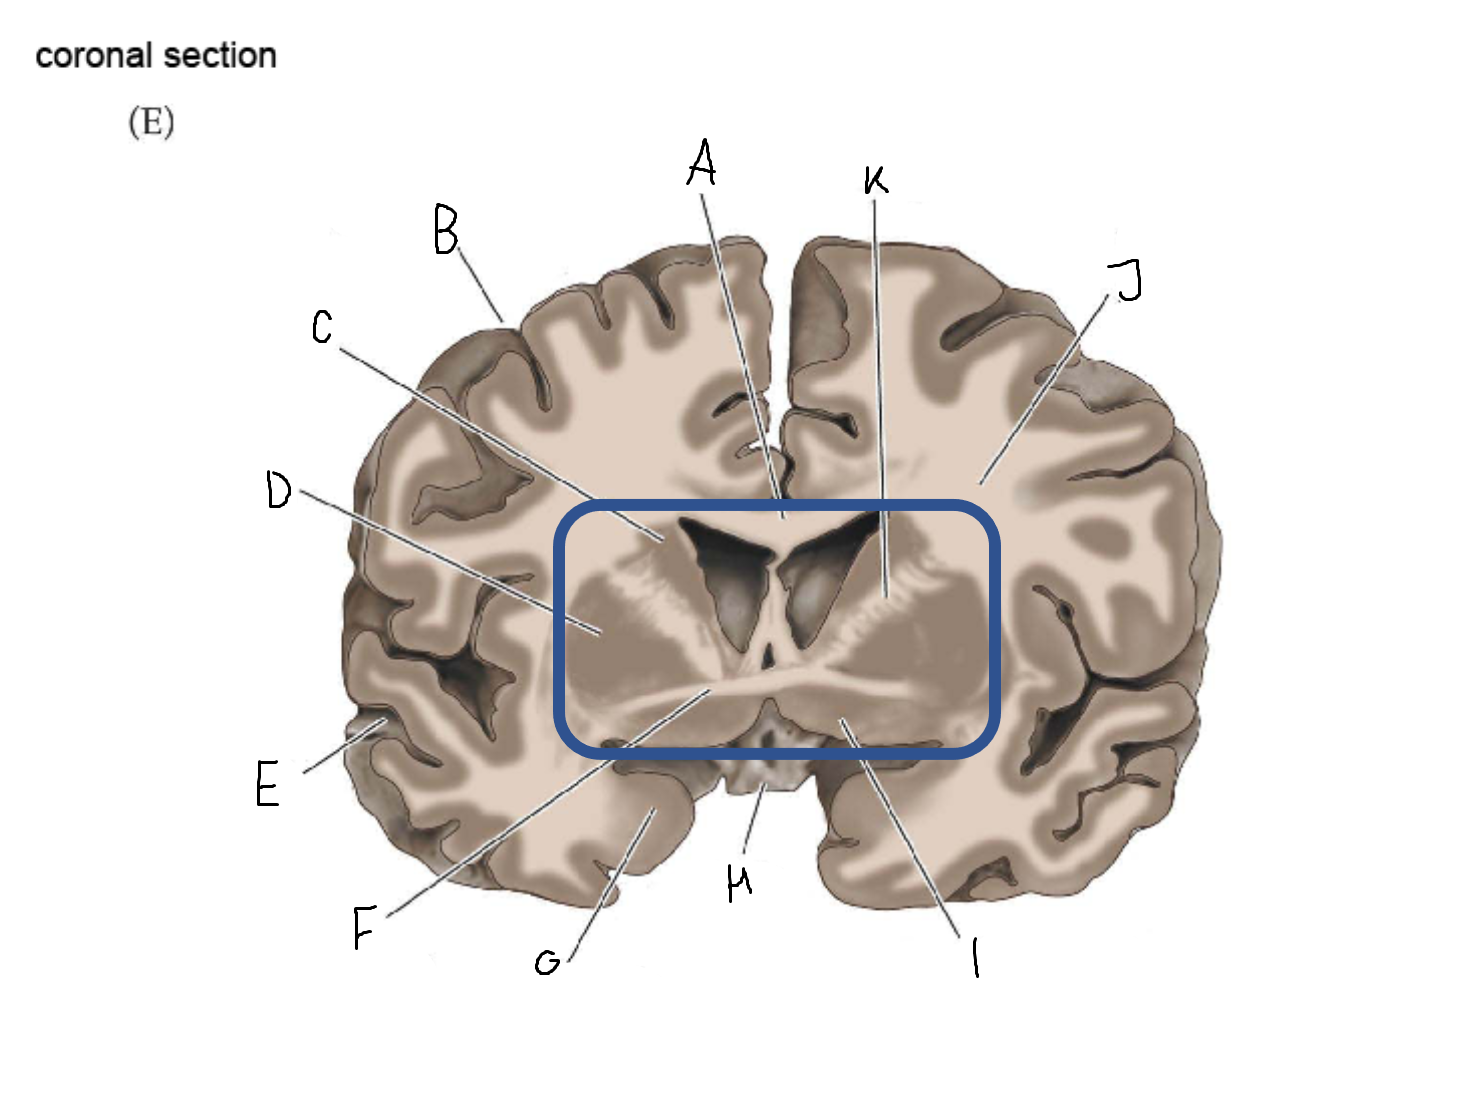

caudate nucleus head

A

Putamen

B

caudate nucleus tail

C

Lateral ventricle

D

caudate nucleus body

E

internal capsule

F

A

internal capsule (anterior limb)

B

caudate nucleus body

C

caudate nucleus head

D

putamen

E

caudate nucleus tail

F

thalamus

G

internal capsule (posterior limb)